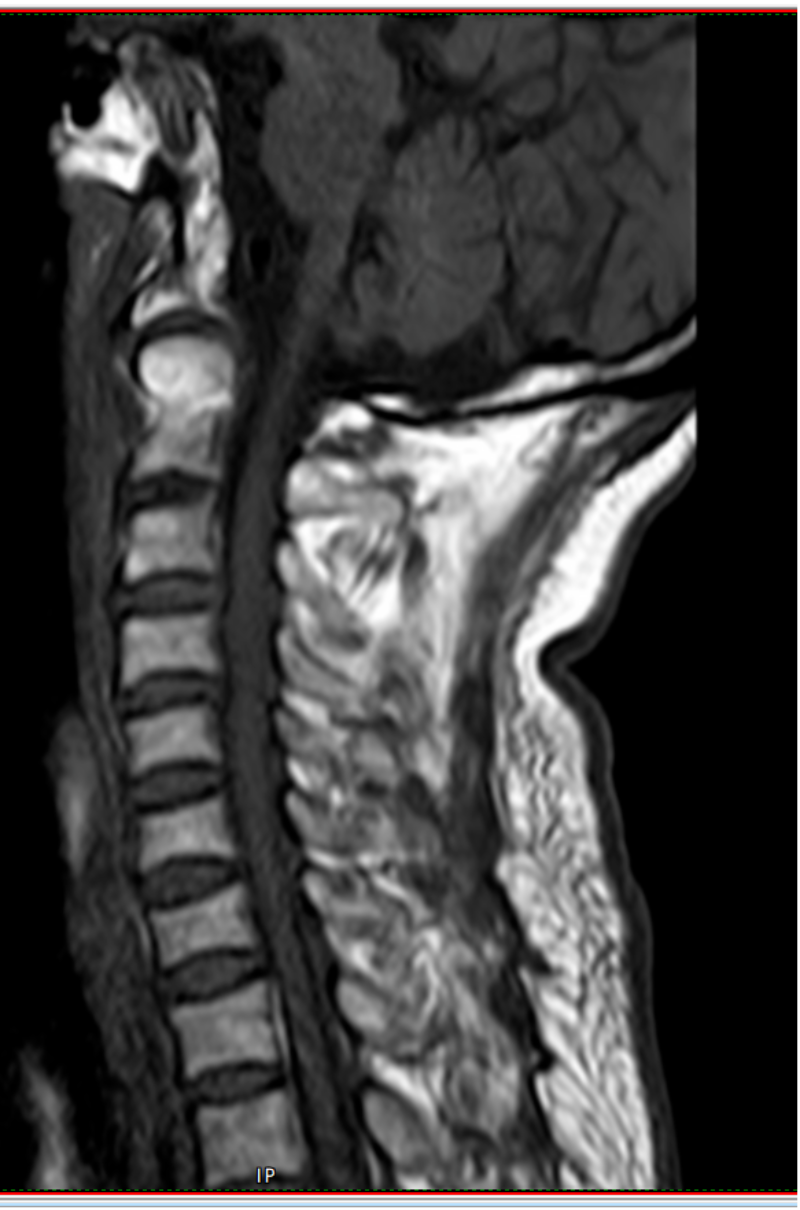

73岁的黄先生因不慎摔倒从山坡上滚下头面部先着地致“寰椎骨折”入住惠州市中心人民医院中文博彩平台分院(中文博彩平台人民医院)脊柱外科。入院时患者颈肩部、双上臂疼痛剧烈,伴有双上肢麻木感,活动受限。

初期给予黄先生颈托外固定保守治疗,但考虑颈托限制活动不稳定,容易松动,上颈椎解剖位置关系特殊,位置重要,且邻近解剖关系复杂,病变引起的临床症状严重、多变及轻重不一,愈合率低,其中老年患者保守治疗的死亡率高达21%-33.3%,是年轻患者的21倍,而该骨折手术风险大、技术难度高,患者及家属对手术心存顾虑。面对此困境,姚仕奋主任凭借丰富的临床经验,深入分析了患者的病情及身体状况,经过多次科室讨论,建议黄先生进行寰椎骨折闭合复位halo架外固定术治疗,halo架无需手术,避免上颈椎手术的高风险,且能提供稳定的颈椎外固定,治疗效果确切,并且避免患者长期卧床而导致各种并发症。

高位颈椎骨折,特别是涉及寰枢椎的骨折,是一种严重的医疗状况,因为它直接影响到颈椎的结构和颈椎脊髓的完整性。这种类型的骨折需要高度专业的医疗干预,以最小化神经系统损伤的风险并确保稳定的骨折愈合。若不及时处理,随着病情进展压迫脊髓,将会危及生命。

姚仕奋表示,黄先生的寰椎骨折属于高位颈椎损伤,不幸中的万幸是受伤后颈椎骨折后释放了大部分暴力,虽然寰椎前弓粉碎性骨折比较严重,但颈椎脊髓反而受伤较轻,经过及时恰当治疗,预后恢复良好。因此,他提醒,广大市民们要引起高度重视,对于脊柱骨折脊髓损伤患者应及时就近诊治,特别是颈椎受伤后肢体麻木乏力者不要随意移动,需及时送到有脊柱外科专业团队的医院救治,曾出现过病人伤后不恰当搬运及转运而出现症状加重的情况,甚是可惜。